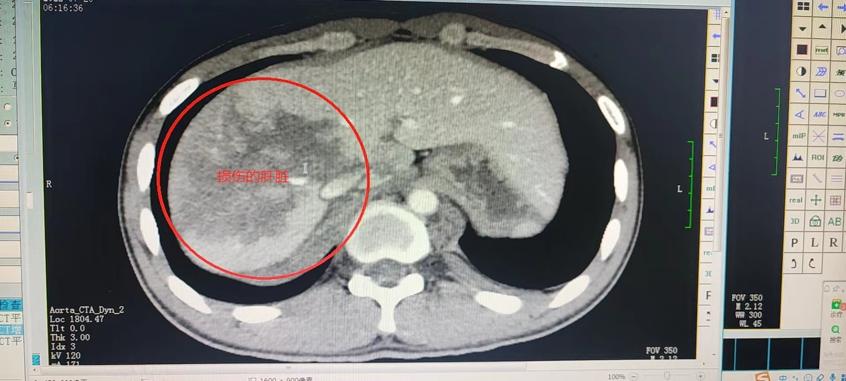

刚送入院时,小尹面色苍白,皮肤湿冷,急诊二部医护人员立即为小尹开放了绿色通路,在进行了一系列抢救与检查后,小尹被确诊为肝挫裂伤,胸主动脉旁出血,口唇多处穿透伤,牙多处断裂。其中,最严重的肝挫裂伤极可能要切除大部分肝脏,小尹立刻被转入急诊二部ICU继续观察与治疗。

受伤这么严重,小尹父母紧张万分。急诊二部曹彦主任、医疗组长靖颖霞副主任医师、侯琨副主任医师及其医疗团队为了挽救这一年轻的生命,对其病情进行了紧急讨论。由于小尹有牙齿多根断裂、咽喉异物感、唇裂伤张口困难,若咽喉部有断裂的牙齿,随时可能进入气管内导致窒息。医务人员立即为小尹进行了床旁纤维喉镜检查,清除了咽喉部异物。由于有大面积肝挫裂伤、主动脉血肿随时可能大出血,危及生命,急诊二部立即邀请肝胆外科、普外、胸外、介入、口腔、耳鼻喉等多个学科联合诊疗,制定最佳方案。最终,在急诊ICU经过精心治疗与护理后,小尹生命体征平稳,肝脏各项指标也在慢慢恢复正常,顺利保住了肝脏。